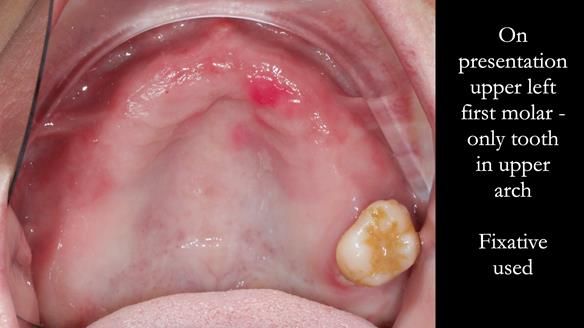

Zoe was referred to me for specialist prosthodontics by her general dentist, after unsuccessful attempts to provide a denture because of fractures, looseness and discomfort.

The upper left first molar demonstrated excellent condition, with no signs of mobility, caries, or periodontal issues.

Visual screening for oral cancer revealed healthy soft tissues—a routine assessment for all patients.